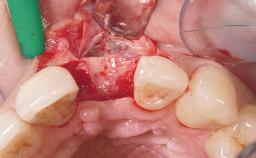

Immediate Placement of an Implant in a Maxillary Right Central Incisor Site

A 30-year-old female patient was referred to the office for the treatment of tooth 11. Her chief concern at the initial visit was to inquire, “Why is my tooth pink?” Upon clinical examination, it was determined that tooth 11 had a previous history of trauma and that the clinical crown had become noticeably pink in color as a result of internal resorption. This diagnosis was confirmed radiographically, indicating a large radiolucency involving the central and distal portions of the clinical crown. It was determined that restoration of this tooth was not possible, and that extraction was indicated. The presence of a mid-line diastema, which the patient wanted to reproduce, directed the treatment plan for tooth replacement utilizing a dental implant.

Bone Augmentation Horizontal|Simultaneous

Augmentation Materials Autogenous chips|Membrane

Placement Protocol Immediate implant placement